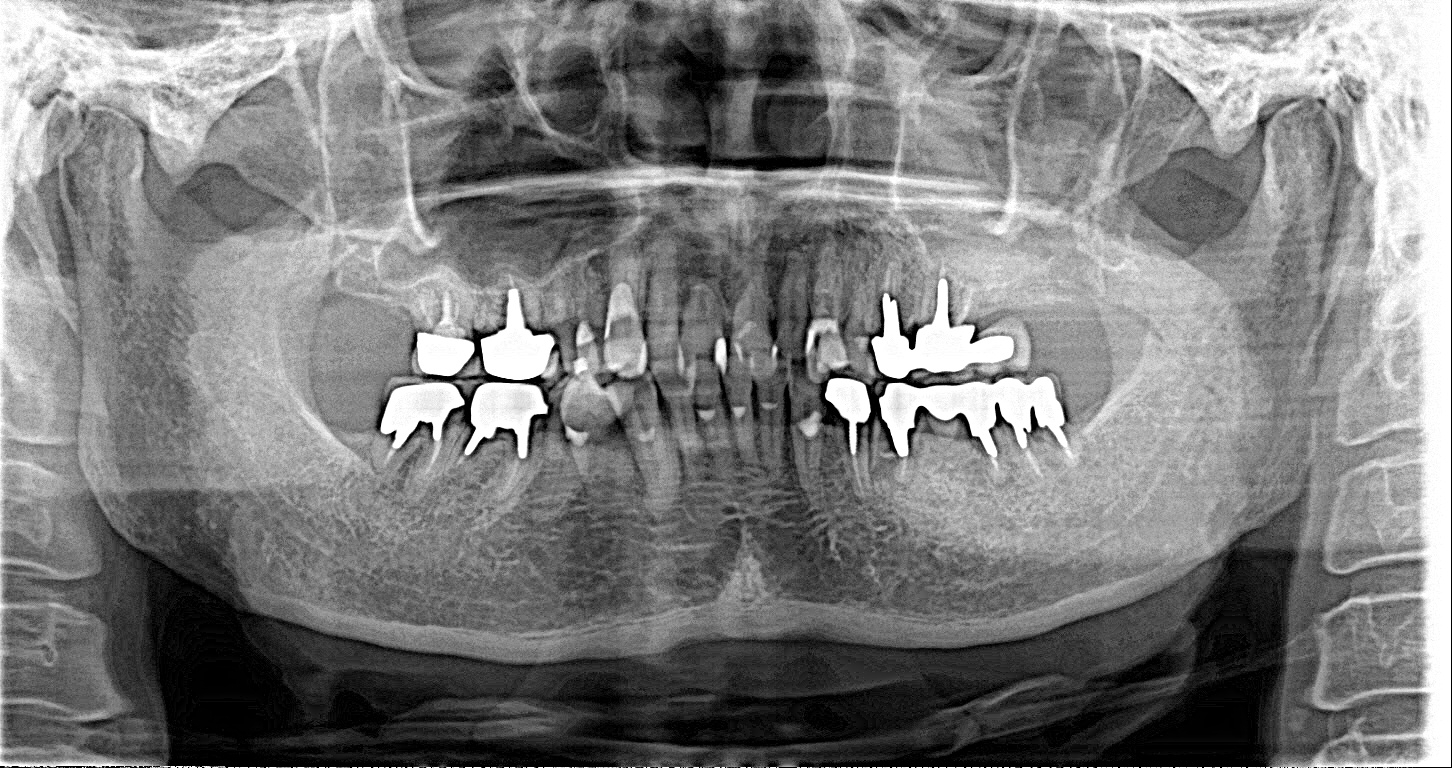

この患者様は、右上の奥歯の歯茎から出血してくるとのことで来院されました。歯周組織検査とレントゲンで診断を行った結果、重度の歯槽膿漏が認められ、保存不可能の為、抜歯になると伝えたところ、入れ歯は絶対に嫌だと言われたので、インプラント治療となりました。CT撮影を行ったところ、上顎洞底までの距離が3ミリ程度しかなかったのですが、骨が固く、フィクスチャーの一次固定が良好だったので、開窓法による上顎洞底挙上術とフィクスチャーの埋入を同時に行いました。約10カ月後に二次手術を行い、上部構造をセットしました。また、右下の臼歯部のブリッジにも大きな二次カリエスが認められ、7番の遠心根が抜歯になり、6番、7番にインプラント治療をしました。